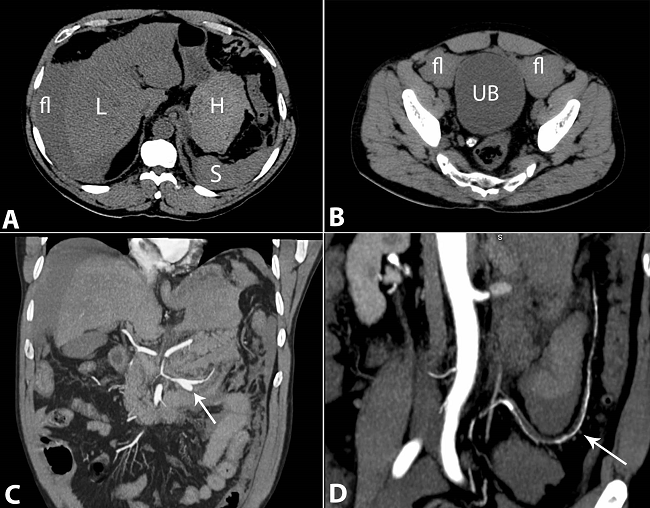

A 61-year-old Caucasian man sought medical care complaining of colicky hypogastric pain accompanied by nausea and hyperdefecation over the past 2 days. The initial clinical evaluation was unremarkable except for mild hypertension. The patient denied any previous diagnosis, but was a tobacco smoker of 10 packs/year. The clinical complaint worsened in the hours after admission with vomiting and fever despite the administration of painkillers, scopolamine, and metoclopramide concomitant with the rise in blood pressure. A few hours after admission, the patient presented a decreased level of consciousness accompanied by cold extremities, tachycardia, and severe hypotension (blood pressure of 50/30 mmHg). The cardiac, pulmonary examination results were average, but the abdomen was diffusely tender, and a crural hernia was easily reducible. Rectal examination was normal, and the patients' clinical status improved with saline volume resuscitation. Laboratory work-up showed normocytic normochromic anemia (hemoglobin: 7.8 g/dL; reference value [RV]: 13-15 g/dL), a normal remaining blood cell count, hyperglycemia (glucose: 276 mg/dL; RV: < 100 mg/dL), prolonged prothrombin time (INR = 1.69; RV: 1.0), and metabolic acidosis (pH = 7.26 with HCO3 = 12 mEq/L; RV: 14 mEq/L). Electrolytes, renal function tests, amylase, lipase, liver enzymes, and myocardium necrosis markers were normal. The electrocardiogram showed sinus tachycardia. The multidetector abdominal computed tomography showed, in the arterial phase, the presence of a hyperattenuating fluid in the epiplon retrocavity (Figure 1A) peripancreatic regions, and within the free abdominal cavity, consistent with intra-abdominal hemorrhage (Figure 1A, B). The angiographic study showed signs of small- and medium-sized vessels arteriopathy. Several branches of the celiac trunk, and the superior and inferior mesenteric arteries, showed diffuse caliber reduction, contour irregularity associated with narrowing and dilation, as well as segmental thrombosis. Saccular aneurysms were also found in the branches of both renal arteries close to the hilum and in the medium colic artery that emerged from the celiac trunk, which was most likely the origin of the hemoperitoneum. Active bleeding signs were not identified during the tomographic examination (Figure 1C, D; Figure 2).